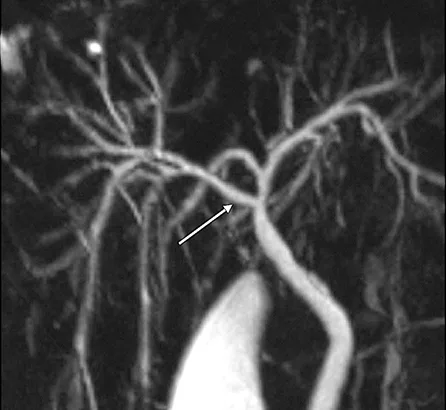

Le diagnostic positif de maladie de Caroli repose sur la cholangio-IRM. Celle-ci met en évidence de volumineuses dilatations kystiques des VBIH, en communication avec le reste de l’arbre biliaire (figure 7A). Il est fréquent de visualiser des calculs au sein des dilatations kystiques (figure 7B). Après injection de produit de contraste, il est classique de visualiser un vaisseau réhaussé (branche de la veine porte ou de l’artère hépatique) au sein de la dilatation kystique (figure 7C). Ce signe radiologique dit « central du point » (central dot sign), témoin d’une malformation de la plaque ductale, est pathognomique de la maladie de Caroli. Dans la maladie de Caroli isolée, les dilatations kystiques peuvent être localisées au niveau d’un lobe ou d’un segment hépatique, alors qu’elles sont généralement diffuses dans le cadre du syndrome de Caroli (tableau 1). Concernant le diagnostic de FHC, l’apport de l’imagerie est plus limité, mais permet d’évaluer la présence de signes radiologiques d’HTP (splénomégalie, voies de dérivations porto-systémiques). Il peut néanmoins exister des lésions biliaires associées à la FHC isolée sans syndrome de Caroli, à type de cholangite ou d’augmentation de volume de la vésicule biliaire (23).

Figure 7 : Visualisation par IRM hépatique de lésions caractéristiques de maladie de Caroli : dilatation kystiques (étoiles) des canaux biliaires intra-hépatiques (A) ; présence de calculs (flèches) au sein des dilatations kystiques biliaires (B) ; central dot sign : vaisseau réhaussé au sein d’une dilatation kystique (flèche) (C)